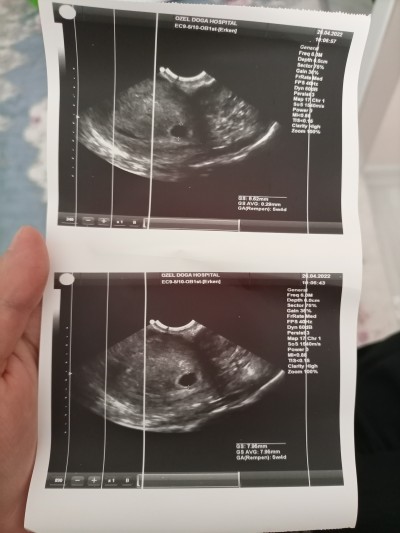

Bugün ilkkez ultrason muayenesi yapıldı alttan keseyi gördük ama bebeği görmedik doktor haftaya görünür dedi ama neden böyle görünmedi kafam takıldı, acaba döllenme mi geç oldu

Gebelik haftası 5+4